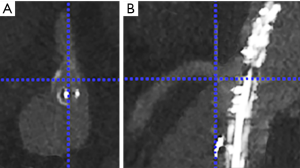

Landmarking of the ostium of the target vessels: The ostium of the celiac artery (CA), superior mesenteric artery (SMA), left renal artery (LRA) and right renal artery (RRA) were landmarked in both the CTA dataset and the ceCBCT dataset. Landmarking was performed by two researchers: one vascular surgeon who performed >250 FEVAR and BEVAR procedures and one experienced researcher involved in clinical imaging during >100 FEVAR and BEVAR procedures. The landmarks were placed in the caudal edge of the ostium of the vessel, as this edge could be distinguished consistently. This landmark was placed by first selecting the centre of the ostium of the target vessel in an axial reconstruction plane, followed by selection of the distal edge of the ostium of the vessel in the sagittal (for CA and SMA) or coronal reconstruction plane (for RRA and LRA) as shown in Figure 2. All measurements were performed using an enlarged zoom of 5 px/mm to keep measurements consistent. Each of these landmarks was recorded as a 3D coordinate. Inter observer variability was checked using the inter class correlation of both observers.